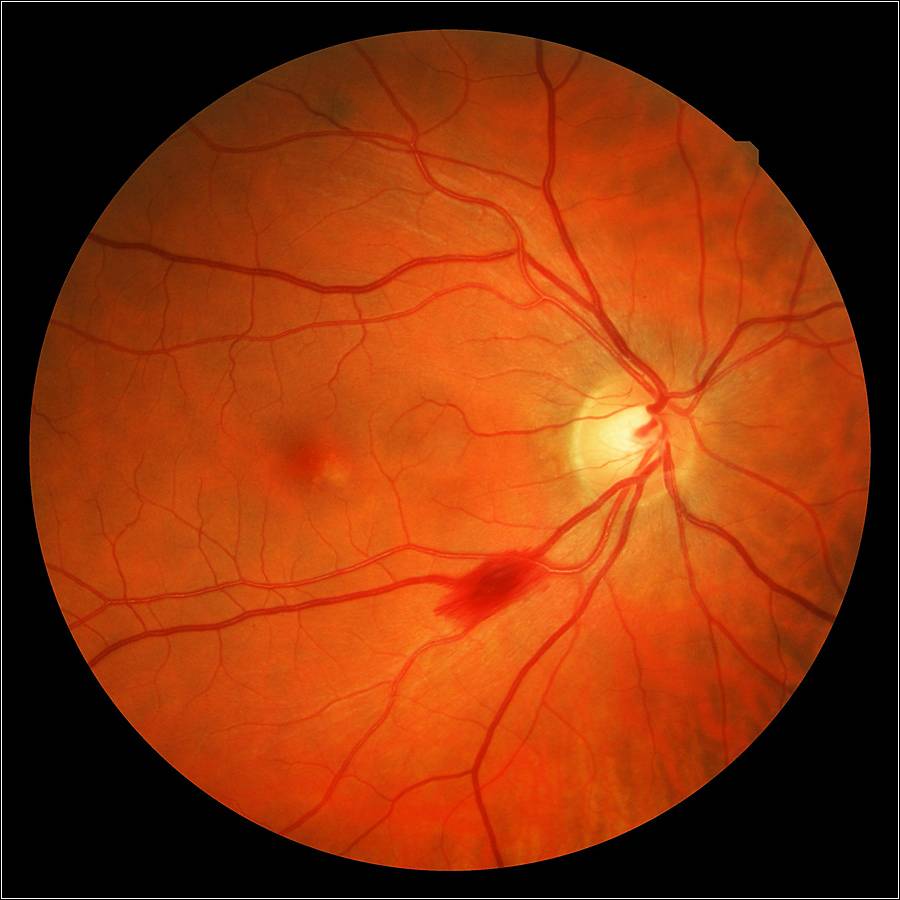

Атрофия зрительного нерва Лебера: Симптомы и лечение